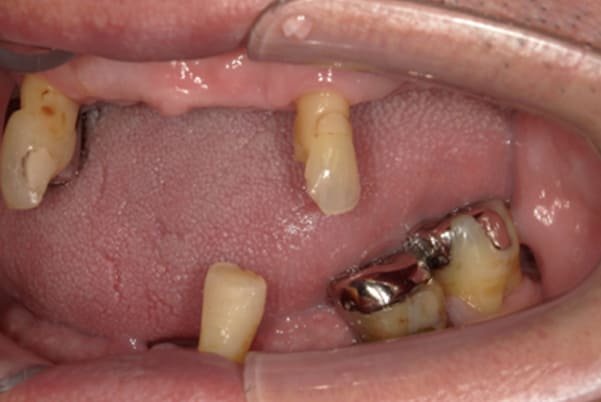

上顎治療前

-

上顎治療後

根のみの7本は虫歯にもなっており歯肉は腫れあがっています。

残りの歯もレントゲンで重度の歯周炎によりぐらぐらな状態でした。

下顎治療前

下顎治療後

治療前の入れ歯の奥歯は、治療後の義歯と比較しても分かるように、歯が削れ平らになった状態です。

これにより奥歯のかみ合わせは低くなり、前歯のみが強くあたり、かみ合わせにより上の前歯大きな負担がかかっていたことにより、上の前歯が折れたことが考えられます。